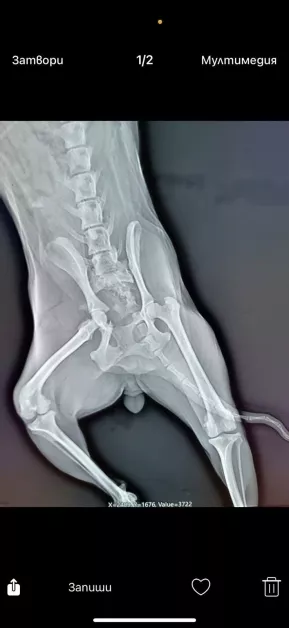

Малко кученце, наречено Пипи, беше открито блъснато в Пловдив и се бори за живота си. Животното е с тежки травми на гръбнака и таза и в момента не може да се изправи самостоятелно. Според снимките, направени след инцидента, състоянието ѝ е сериозно.

За да бъде прието и оперирано в клиника „Провет Тракия“, Пипи се нуждае незабавно от средства за покриване на част от натрупаните задължения – поне 1000 лева, както и предплащане на операцията и последващ престой на стойност около 1600 лева.